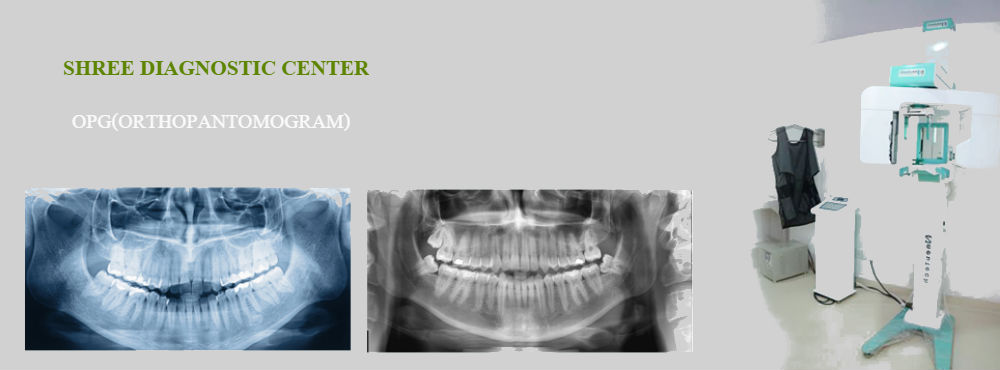

An OPG is a panoramic or wide view x-ray of the lower face, which displays all the teeth of the upper and lower jaw on a single film. It demonstrates the number, position and growth of all the teeth including those that have not yet surfaced or erupted. It is different from the small close up x-rays dentists take of individual teeth. An OPG may also reveal problems with the jawbone and the joint which connects the jawbone to the head, called the Temporomandibular joint or TMJ. An OPG may be requested for the planning of orthodontic treatment, for assessment of wisdom teeth or for a general overview of the teeth and the bone which supports the teeth.

You may be asked to remove jewellery, eyeglasses, and any metal objects that may obscure the images. You will be asked to stand with your face resting on a small shelf and to bite gently on a sterile mouth piece to steady your head. It is important to stay very still while the x-ray is taken. You will not feel any discomfort during the procedure.